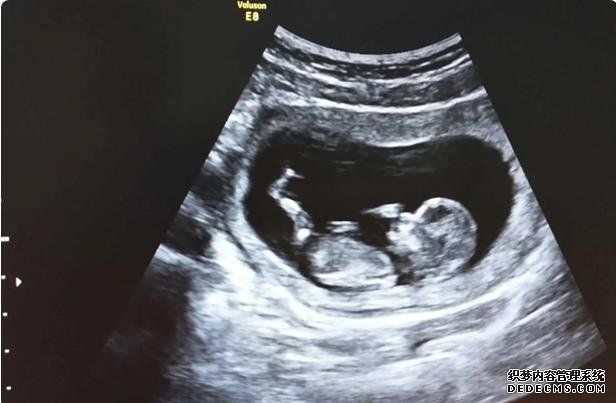

在胡主任那里看诊了之后,现在有一个比天使还可爱的孩子!她就是我生命的全部!谢谢胡妈妈送子。